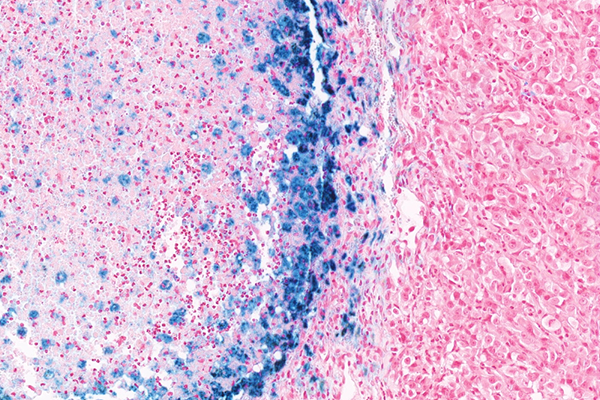

Special staining